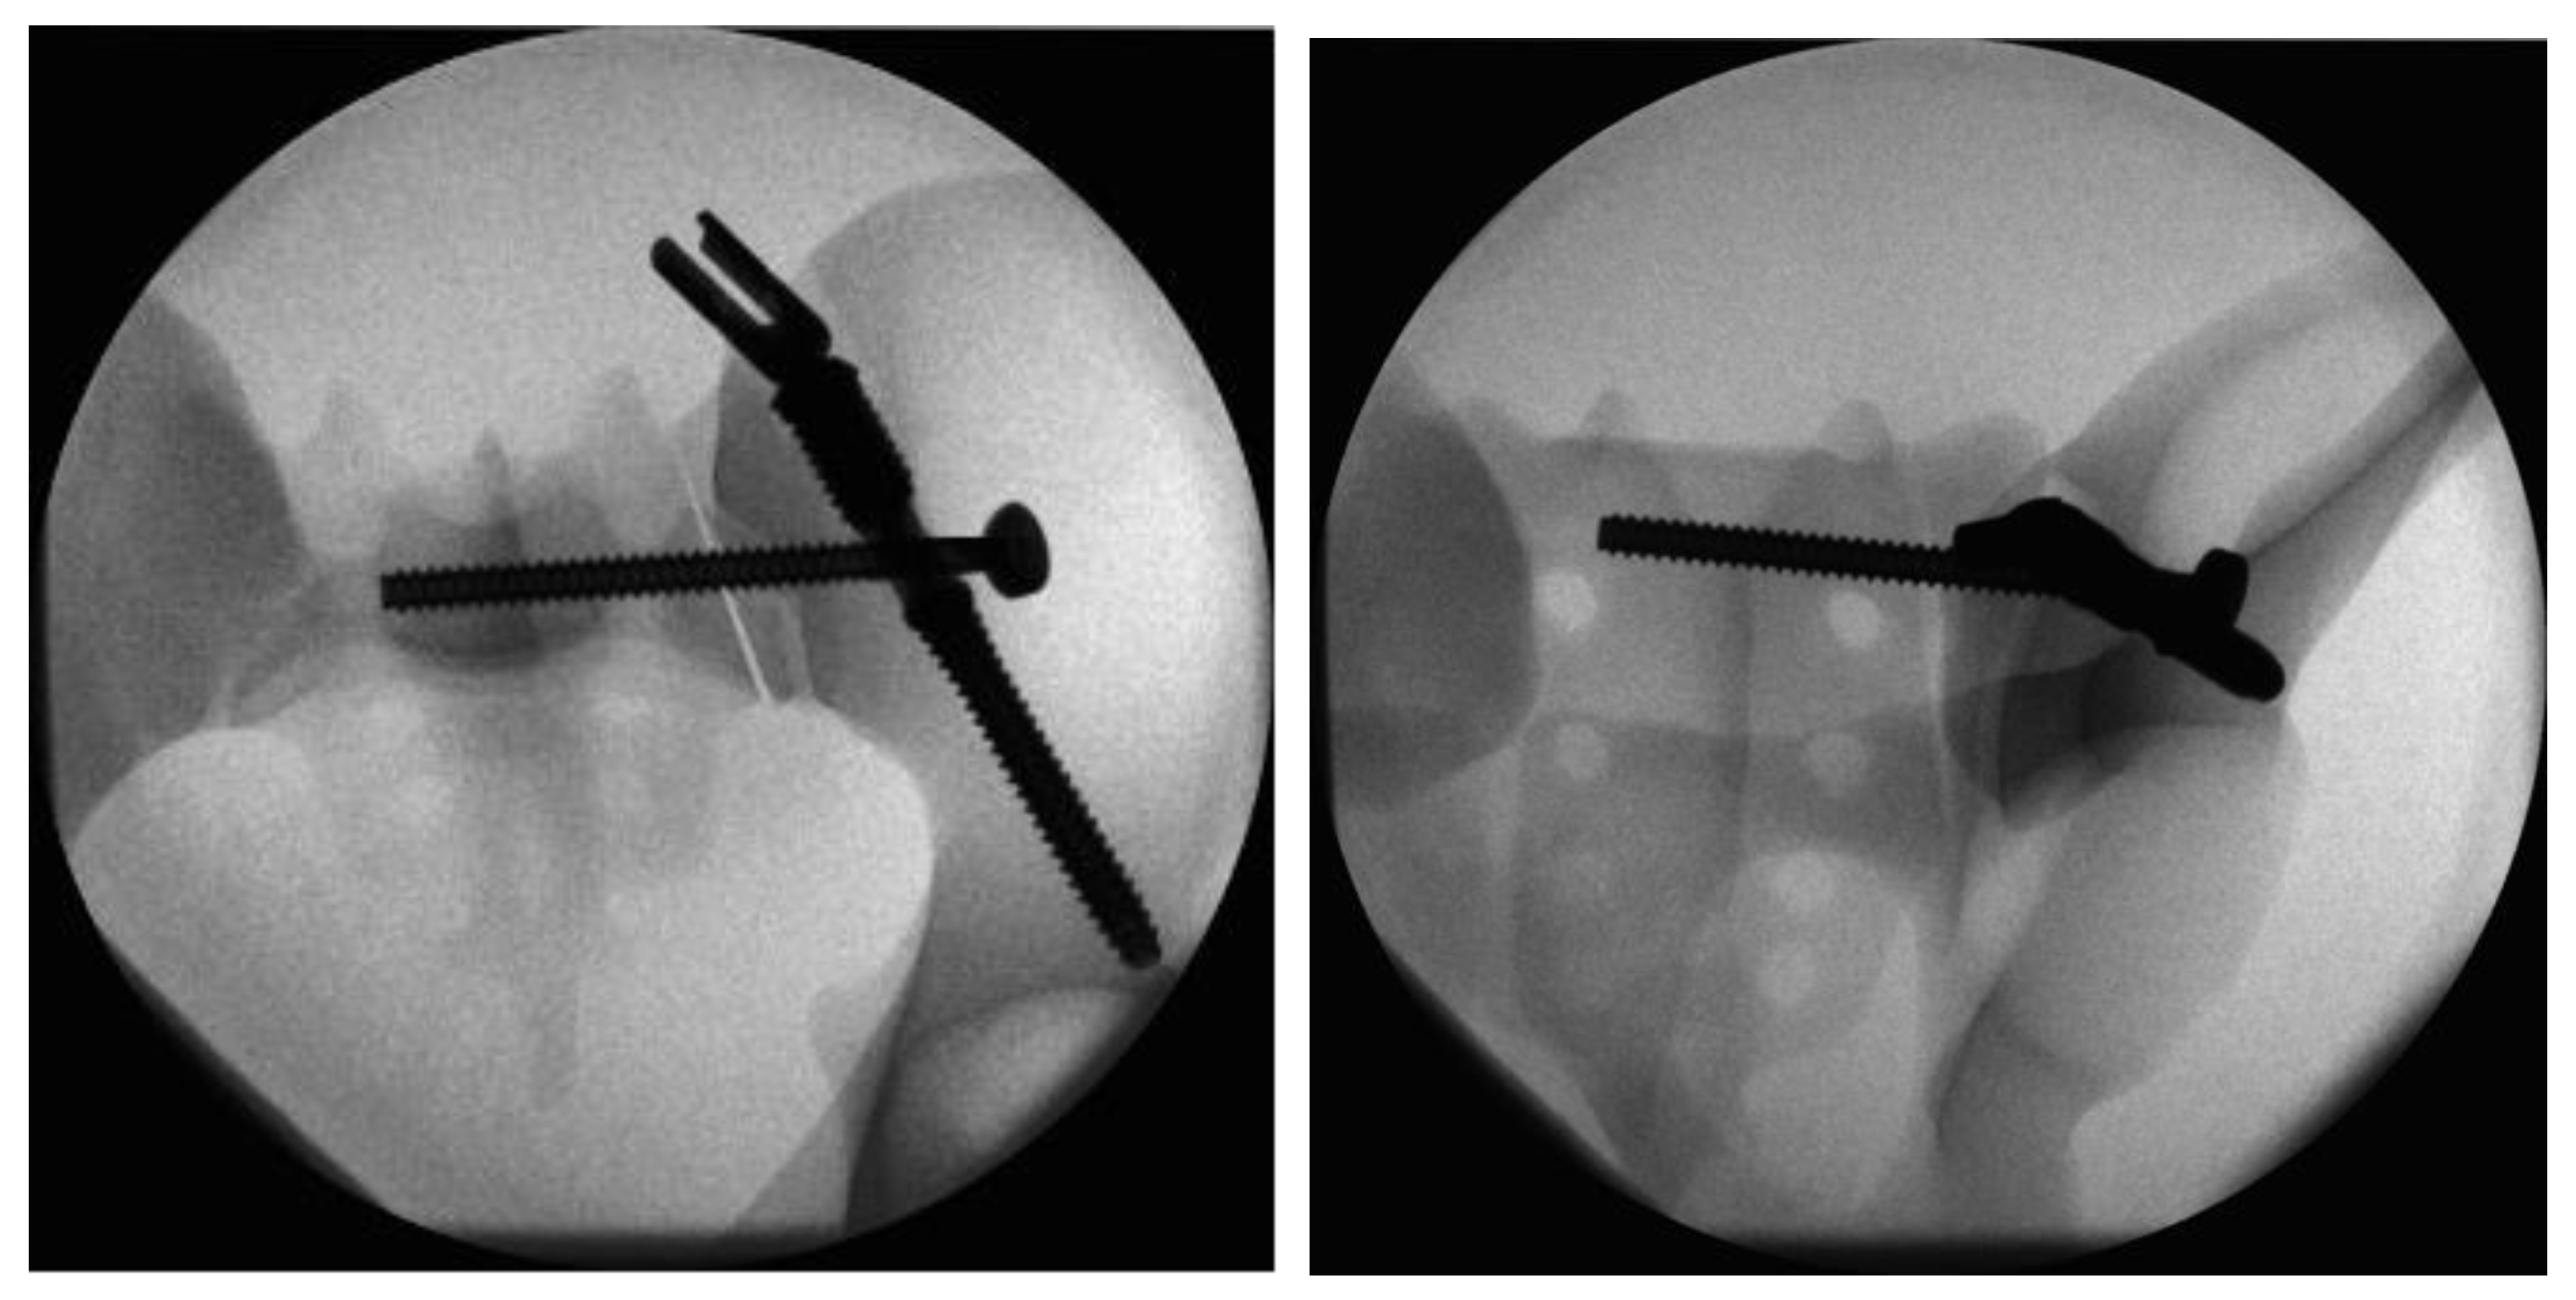

Figure 4.

Radiographs in two planes of the conventional triangular fixation with the sacroiliac screw separate from the iliac screw in a more cranial position.